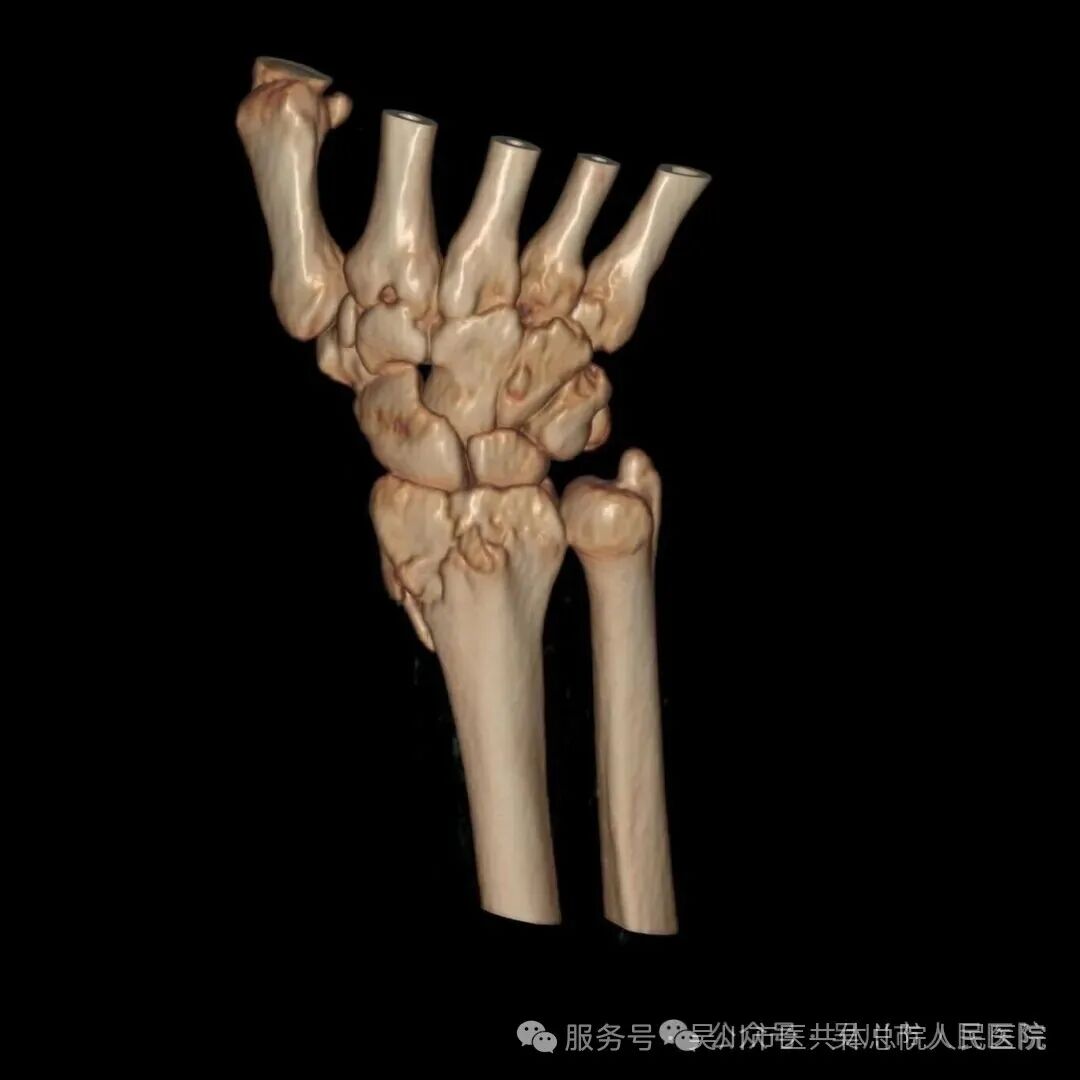

而如今,搭乘“百千万工程”优质医疗资源下沉的春风,我院骨外科已具备开展复杂骨折微创手术的能力,让潘阿姨实现了“家门口看好病”的心愿。被紧急送医后,经细致查体及影像检查,CT结果显示其右腕为粉碎性骨折,骨质碎裂,骨折线呈不规则形,关节面受到累及,若治疗不当极易引发创伤性关节炎,导致后续关节疼痛与活动受限。

结合潘阿姨的年龄与身体状况,王井旺率手术团队经过缜密讨论,决定采用微创手术治疗方案——依托“百千万工程”专项资助配备的高精度骨折复位设备,在精准定位下实现骨折端解剖复位,再用钛合金钢板进行稳固内固定。该部位骨折若处理不佳,将严重影响手腕功能。面对潘阿姨的病情与忧虑,骨一科团队快速响应,曾文晓副主任医师、欧春云副护士长、王井旺耐心向患者及家属详解病情,舒缓家属焦虑情绪。